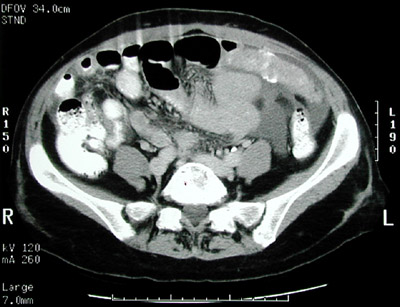

| This abdominal CT scan demonstrates a metastasis in a thickened mesentery as well as metastases with calcifications in a case of seeding of serous cystadenocarcinoma from the ovary. Much smaller calcifications appear microscopically as psammoma bodies. Ascitic fluid is seen here, too. |